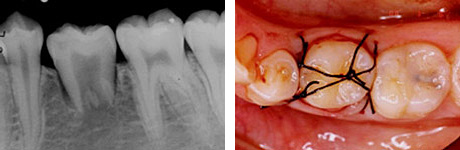

左:移植直後のエックス線写真。

右:移植後1ヶ月。

根管治療直後。歯根が完成している歯を移植歯として用いた場合、歯の神経はつながらないので、このように神経の治療が必要になります。

移植後4ヶ月。

移植歯はコンポジットレジンで修復が行われています。